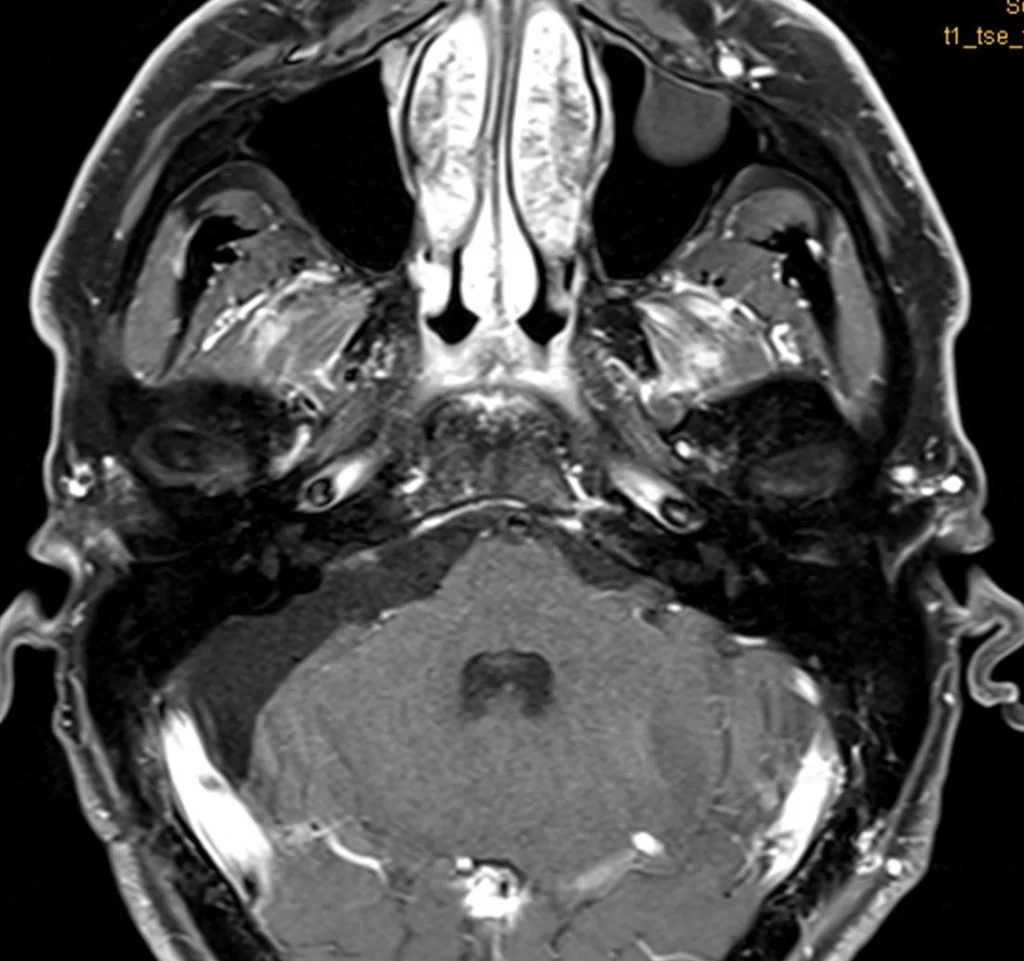

Η μετεγχειρητική μαγνητική τομογραφία εγκεφάλου δείχνει ένα εξαιρετικό αποτέλεσμα, με πλήρη αφαίρεση της βλάβης. Η ιστολογική ανέδειξε μηνιγγίωμα WHO I.

O ασθενής ανάρρωσε άμεσα και πλήρως, χωρίς νευρολογικό έλλειμα και εξήλθε του νοσοκομείου την 5η μετεγχειρητική ημέρα.